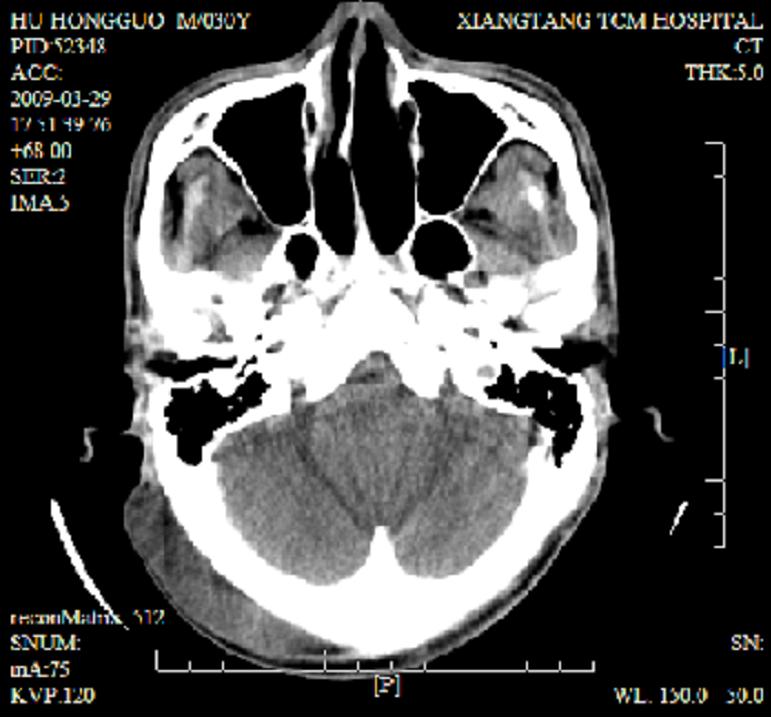

标题: CT19102:颈部肿块

男30y发现肿块3年

多处囊实性肿块,形态欠规则有一定形态,内见点状钙化,以囊变为主,增强后轻度强化,首先考虑神经源性肿瘤如鞘瘤,不除外脉管源性肿瘤如淋巴管瘤(见缝钻及囊性区域太多,如果合并感染完全可以这个影像表现),和海绵状血管瘤,但是血管瘤不太支持因为强化特征和病灶形态不典型.

右侧椎前间隙后部肌间、皮下囊性为主病变,可见分隔和点状钙化,分隔和壁呈轻度环形强化,大部分无强化。形态不规则,有钻缝特点。考虑1 淋巴管瘤合并感染2 血管平滑肌脂肪瘤3 表皮样囊肿4 不除外海绵状血管瘤。